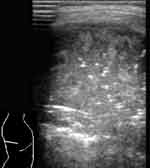

При снижении воздушности легочной ткани вследствие пневмонической инфильтрации или ателектаза, она становится эхографически видимой, имеет пониженную эхогенность и однородную эхоструктуру. Контур пневмонического очага в начале заболевания довольно ровный, форма может быть различной. В случае долевой пневмонии он повторяет форму доли, при сегментарной может иметь пирамидальную форму с основанием, обращенным к плевре, очаговой — неправильную, близкую к округлой. В безвоздушных пневмонических очагах бывают видны эхогенные, ветвящиеся, прерывистые полоски, являющиеся заполненными воздухом бронхами, а так же трубчатые анэхогенные структуры — сосуды или заполненные жидкостью бронхи и реже — тонкие линейные эхогенные полоски — соединительно-тканные межсегментарные перегородки (Рис. 2, 3). Эхогенная полоска плевры над безвоздушным участком (пневмоническим очагом или ателектазом) выглядит гораздо тоньше, чем над воздушным легким. Но это происходит не из-за «истончения плевры» [1], а из-за отсутствия составляющей отражения от поверхности воздушного легкого в комплексе плевральной эхогенной полоски. Пневмонические участки в наших наблюдениях имели несколько пониженную или среднюю эхогенность и не были гиперэхогенными, как указывают некоторые авторы [9, 2]. По мере же пневматизации при рассасывании инфильтрата в них появлялись множественные сливающиеся гиперэхогенные участки пневматизации. А высокая эхогенность при «свежих» пневмониях отмечалась за безвоздушными участками на границе с воздушной легочной тканью вследствие дистального усиления.

[Увеличить]

Рис. 3. Пневмонический очаг с заполненными жидкостью бронхами.